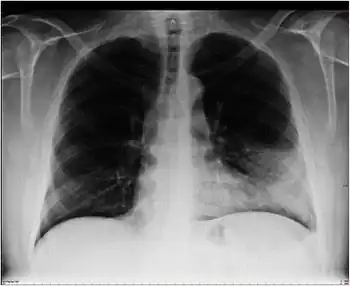

Atypical pneumonia- X-Ray chest showing right peribronchial central infiltrate

Chest radiographs (X-ray photographs) often show a pulmonary infection before physical signs of atypical pneumonia are observable at all.[5] This is occult pneumonia. In general, occult pneumonia is rather often present in patients with pneumonia and can also be caused by Streptococcus pneumoniae, as the decrease of occult pneumonia after vaccination of children with a pneumococcal vaccine suggests.[16][17]

Infiltration commonly begins in the perihilar region (where the bronchus begins) and spreads in a wedge- or fan-shaped fashion toward the periphery of the lung field. The process most often involves the lower lobe, but may affect any lobe or combination of lobes.[5]